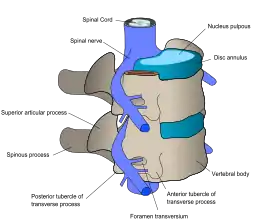

The laminae give attachment to the ligamenta flava, which are ligaments of the spine. There are vertebral notches, each constituted by the shape of the pedicles, which form the intervertebral foramina when [1] vertebrae articulate. These foramina are the entry and exit conduits accommodating the spinal nerves. The body of the vertebra, and it's vertebral arch, form the vertebral foramen, which is the larger, stable and central opening: this accommodates the spinal canal, and encloses and protects the spinal cord.

Every vertebra has a body (vertebral body), which consists of a large anterior middle portion called the centrum (vertebral centrum, plural centra) and a posterior vertebral arch,[3] also called a neural arch.[4] The body is composed of cancellous bone, which is the spongy type of osseous tissue, whose microanatomy has been specifically studied within the pedicle bones.[5] This cancellous bone is in turn, covered by a thin coating of cortical bone (or compact bone), the hard and dense type of osseous tissue. The vertebral arch and processes have thicker coverings of cortical bone. The upper and lower surfaces of the body of the vertebra are flattened and rough in order to give attachment to the intervertebral discs. These surfaces are the vertebral endplates which are in direct contact with the intervertebral discs and form the joint. The endplates are formed from a thickened layer of the cancellous bone of the vertebral body, the top layer being more dense. The endplates function to contain the adjacent discs, to evenly spread the applied loads, and to provide anchorage for the collagen fibers of the disc. They also act as a semi-permeable interface for the exchange of water and solutes.[6]

The vertebral arch is formed by pedicles and laminae. Two pedicles extend from the sides of the vertebral body to join the body to the arch. The pedicles are short thick processes that extend, one from each side, posteriorly, from the junctions of the posteriolateral surfaces of the centrum, on its upper surface. From each pedicle a broad plate, a lamina, projects backwards and medialwards to join and complete the vertebral arch and form the posterior border of the vertebral foramen, which completes the triangle of the vertebral foramen.[7] The upper surfaces of the laminae are rough to give attachment to the ligamenta flava. These ligaments connect the laminae of adjacent vertebra along the length of the spine from the level of the second cervical vertebra. Above and below the pedicles are shallow depressions called vertebral notches (superior and inferior). When the vertebrae articulate the notches align with those on adjacent vertebrae and these form the openings of the intervertebral foramina. The foramina allow the entry and exit of the spinal nerves from each vertebra, together with associated blood vessels. The articulating vertebrae provide a strong pillar of support for the body.

Spinal disc herniation, more commonly called a slipped disc, is the result of a tear in the outer ring (anulus fibrosus) of the intervertebral disc, which lets some of the soft gel-like material, the nucleus pulposus, bulge out in a hernia. This may be treated by a minimally-invasive endoscopic procedure called Tessys method.